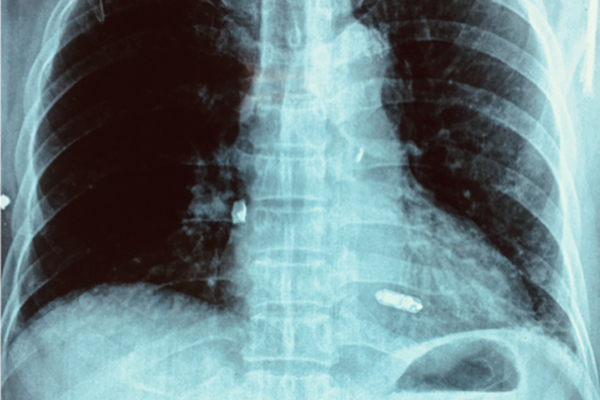

Máy tạo nhịp tim thế hệ cũ với 2 dây điện cực ở nhĩ phải và thất phải

Bệnh nhân đã được cấy máy tạo nhịp 2 buồng tim thông thường với 2 dây điện cực ở nhĩ phải và thất phải. Sau can thiệp, sức khoẻ bệnh nhân dần hồi phục. Tuy nhiên 2 tuần trước khi nhập viện, vùng ngực trái tại vị trí cấy máy tạo nhịp ở dưới da sưng nề đỏ, đau rát nhiều và chảy mủ, lộ máy tạo nhịp làm bệnh nhân rất khó chịu và mệt mỏi.

Hình ảnh máy tạo nhịp tim nhỏ xíu ở thất phải